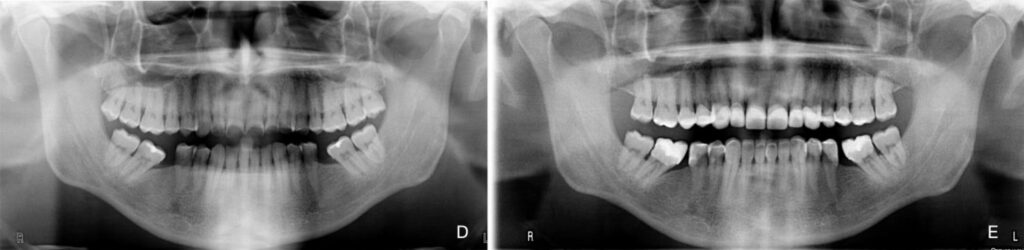

Figure 4. Patient 4: Generalized severe pathological tooth wear (TWES 2.0). (A) Intraoral situation: inverted

occlusal plane shown for a patient with extremely worn anterior teeth associated with a compensatory

extrusion of the mandibular anterior teeth. (B) Occlusion after treatment, highlighting aesthetic

and functional improvement. (C) A 5-year follow-up photograph showing excellent periodontal health

with the total absence of recession, highlighting the maintenance of occlusal contact relationships.

(D) Initial orthopantomography. (E) Final orthopantomography showing the supplementation of

all teeth without endodontic treatments. Felspathic vestibular veneers from 1.2 to 2.2, CAD-CAM

nanoceramic resin palatal veneers from 1.3 to 2.3, and occlusal and vestibular veneers on 1.5, 1.4, 2.4

and 2.5. Finally, lithium disilicate veneers from 3.5 to 4.5 and 3.7, 4.7.